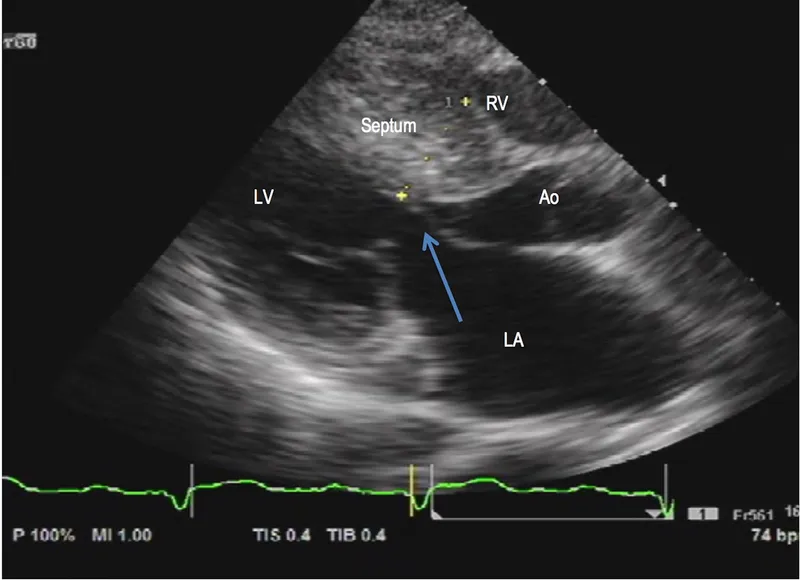

- Echocardiography: LVH ≥15mm (in absence of other cause); ≥13mm in relatives. Shows ASH, SAM, LVOTO gradient, diastolic dysfunction.

- HCM: Asymmetric septal hypertrophy (ASH), LVOTO, SAM. Apical HCM: "ace-of-spades".